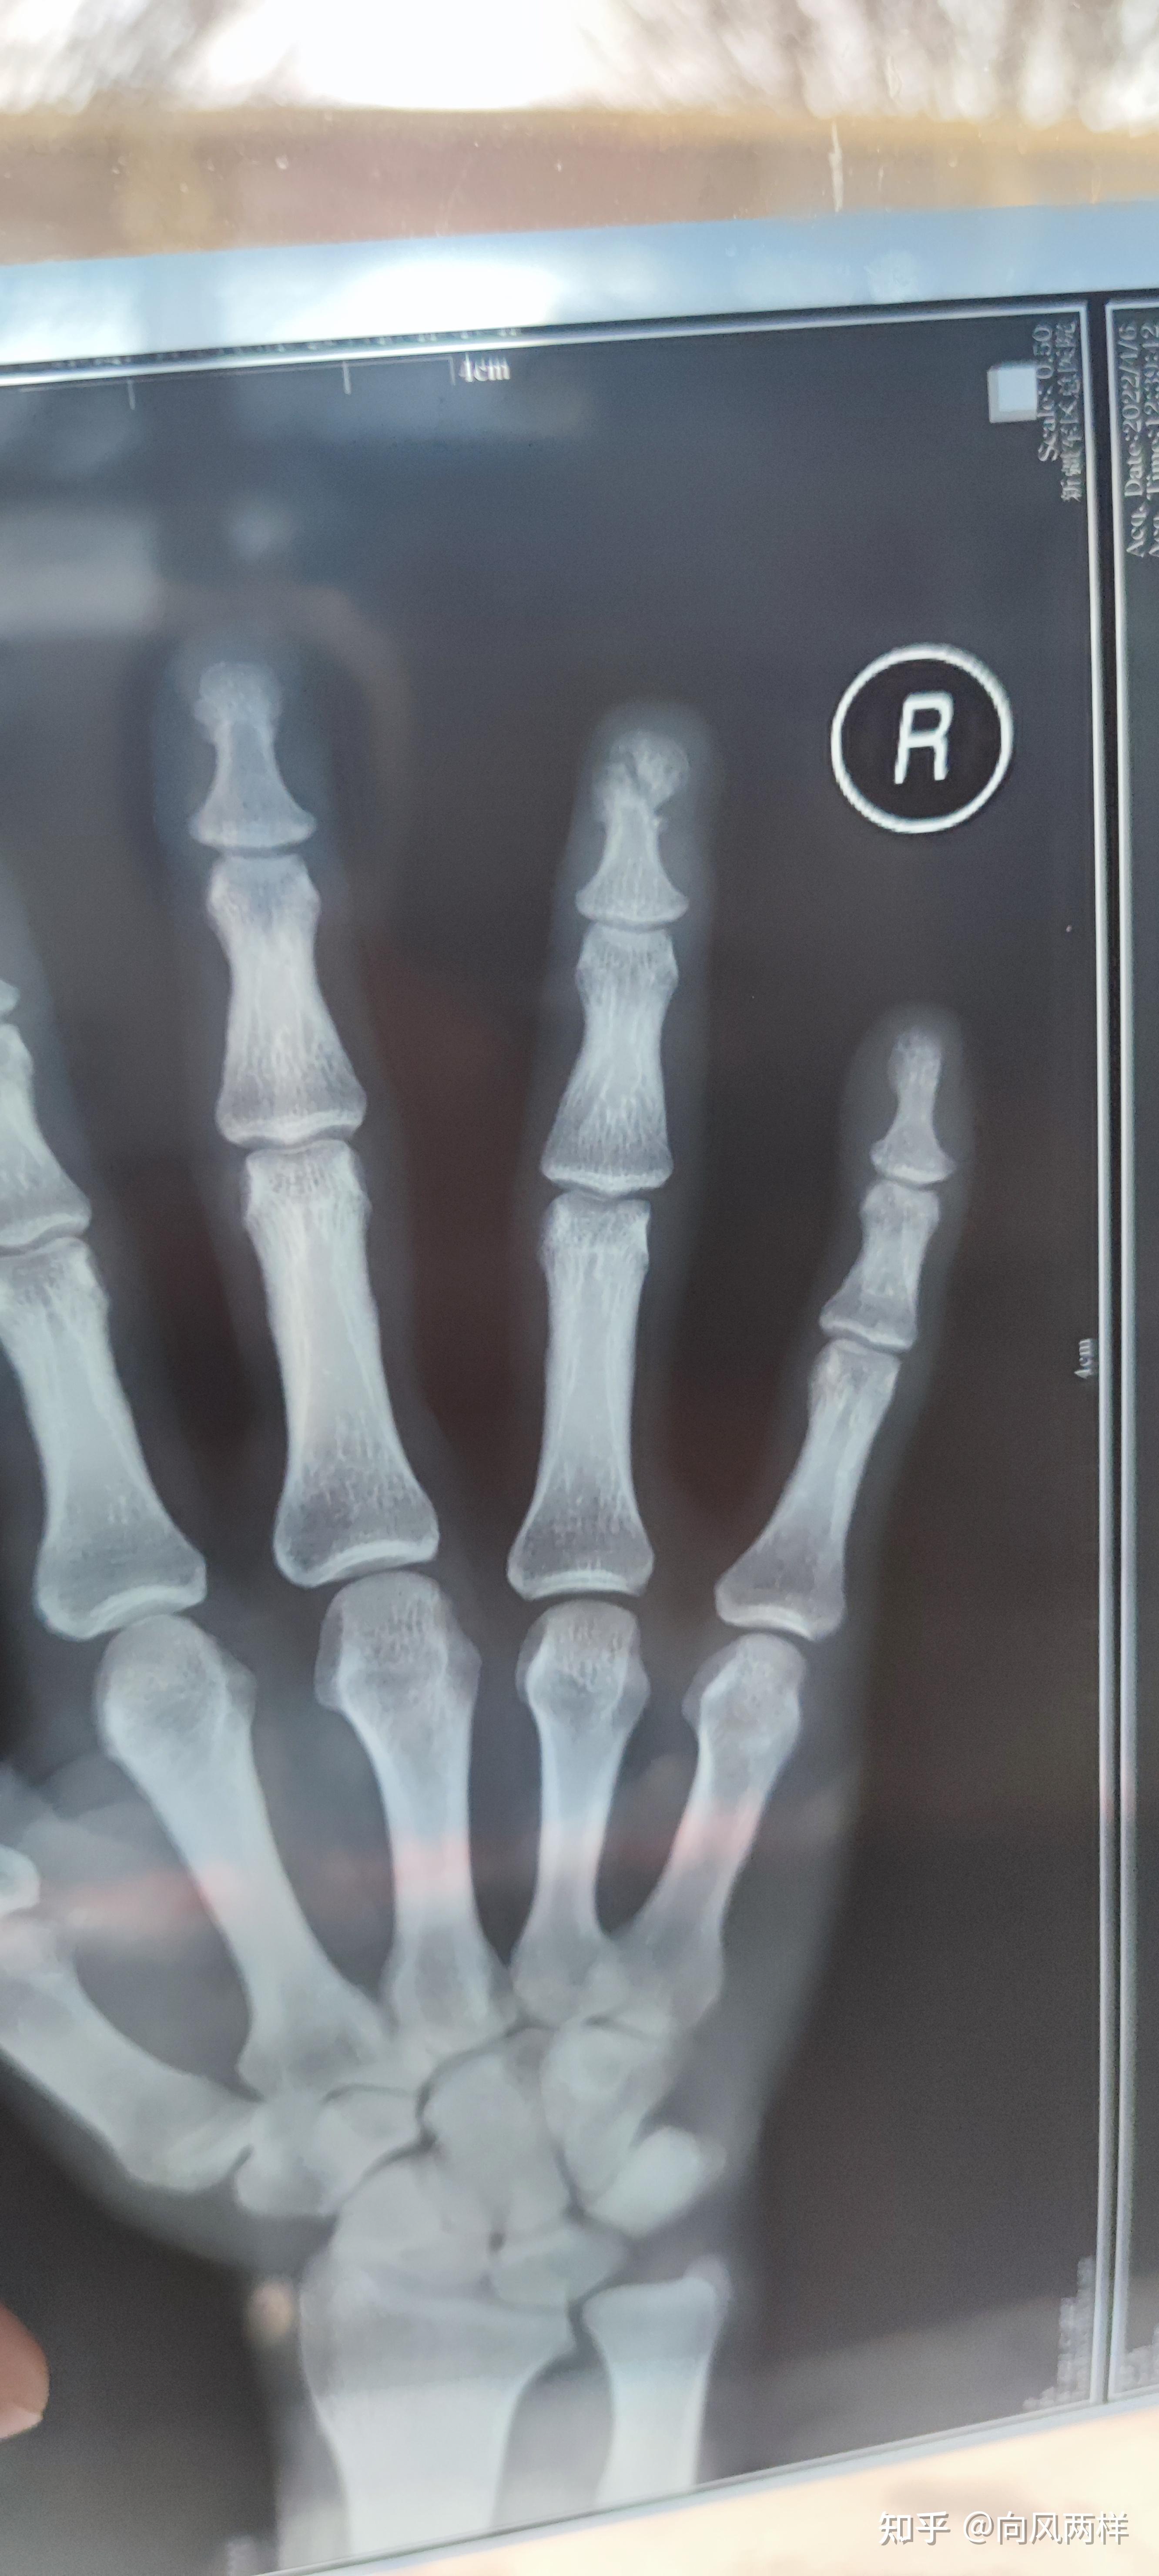

术前检查x拍片示,右食指末节指骨粉碎性骨折.

中指远端指节骨折伴皮肤撕裂